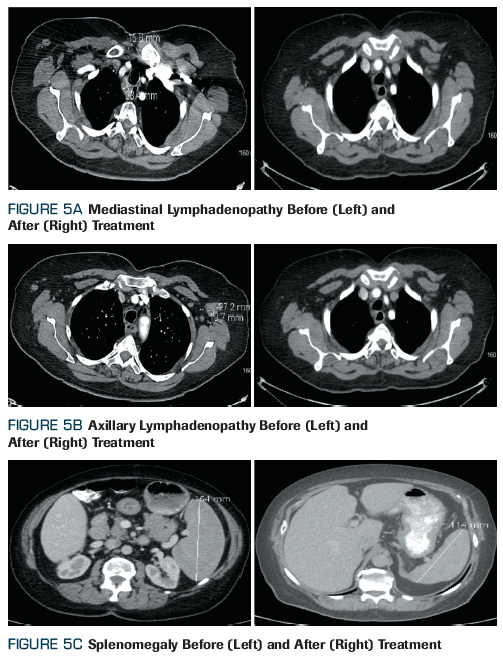

Figure 5. (A) Mediastinal Lymphadenopathy Before (Left) and After (Right) Treatment; (B) Axillary Lymphadenopathy Before (Left) and After (Right) Treatment; (C) Splenomegaly Before (Left) and After (Right) Treatment

The pathology of the skin biopsy was reported to be extranodal marginal zone lymphoma. The patient denied any palpable lumps, night sweats, fevers, or weight loss. A somewhat limited physical examination due to her overweight condition did not reveal lymphadenopathy or organomegaly. Further workup with CT scans of the chest, abdomen, and pelvis revealed axillary, hilar, and mediastinal lymphadenopathy, as well as splenomegaly (Figure 5). A unilateral bone marrow aspiration and biopsy showed involvement by marginal zone lymphoma. The patient was treated with 6 cycles of combination chemotherapy with rituximab, cyclophosphamide, vincristine sulfate, and prednisone (R-CVP) and achieved a complete response.